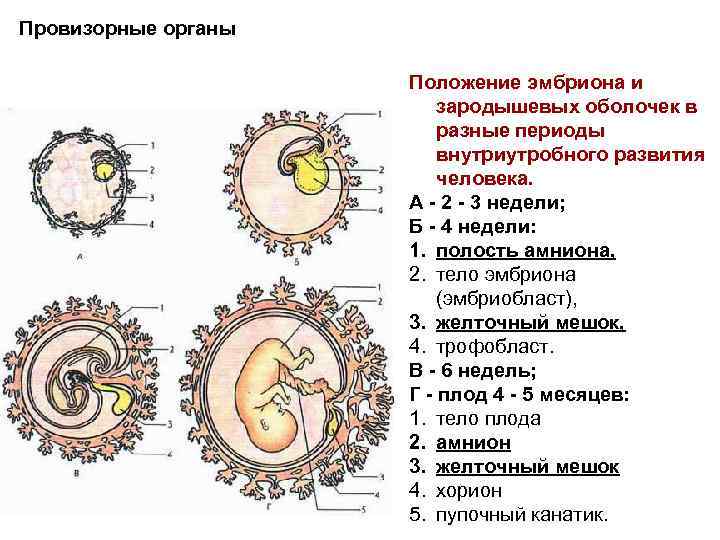

Эмбриональный период: Развитие эмбриона от зачатия до рождения

Раздел: Картинки на заметку